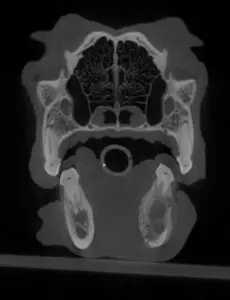

In the following case, the right lower first molar had chronic pulp exposure. This caused an infection in the bone (osteomyelitis) that spread beyond the tooth roots. Although this many changes in the bone can also be due to cancer, a biopsy confirmed that it was just infection. Again, extraction of the tooth fixed the problem, and the dog felt much better afterwards. Antibiotics were used because the infection in the bone was so extensive.